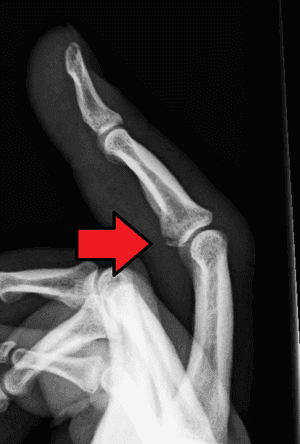

Fracture Dislocation - सांध्यातील एका हाडाला फ्रॅक्चर असल्याने सांधा निखळणे.